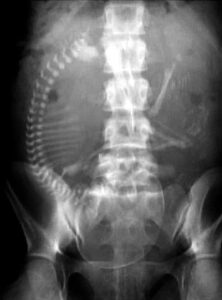

ورغم إنكار المريضة وعدم وجود زواج، قرر الطبيب افتراض حسن النية، والبدء من التشخيص الطبي المنطقي، فطلب أشعة سينية على البطن بوضعيات مختلفة، لاشتباه انسداد معوي، مع وضع في الاعتبار احتمال أن تكون في حالة ولادة كاملة، وأن الجنين مكتمل النمو ولن يتأثر كثيرًا بجرعة الأشعة في تلك اللحظة الحرجة.

جاءت نتيجة الأشعة صادمة وواضحة، هيكل عظمي كامل لجنين داخل الرحم.